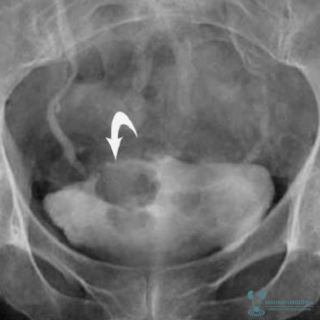

ULTRASONIDO

Constituye uno de los estudios más importantes pues permite el estudio de la pared de la vejiga y nos da alguna información sobre la afección de la vía urinaria superior, aunque en caso de alta sospecha de compromiso de esta, los estudio más relevantes serían el URO TAC o la Urografía Intra Venosa (UIV). Si se detecta una lesión en la vejiga, en principio, no sería necesario la visualización de la misma mediante cistoscopia para proceder a la Exploración Vesical Bajo anestesia.

|

| Ultrasonido en el que se muestra lesión vesical exofítica. |